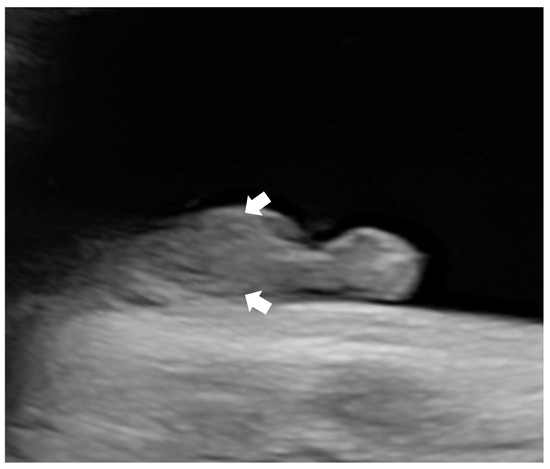

| SUA | N.R. | N.R. | N.R. | N.R. | N.R. | N.R. | - | - | - | - | - | - | - | + |